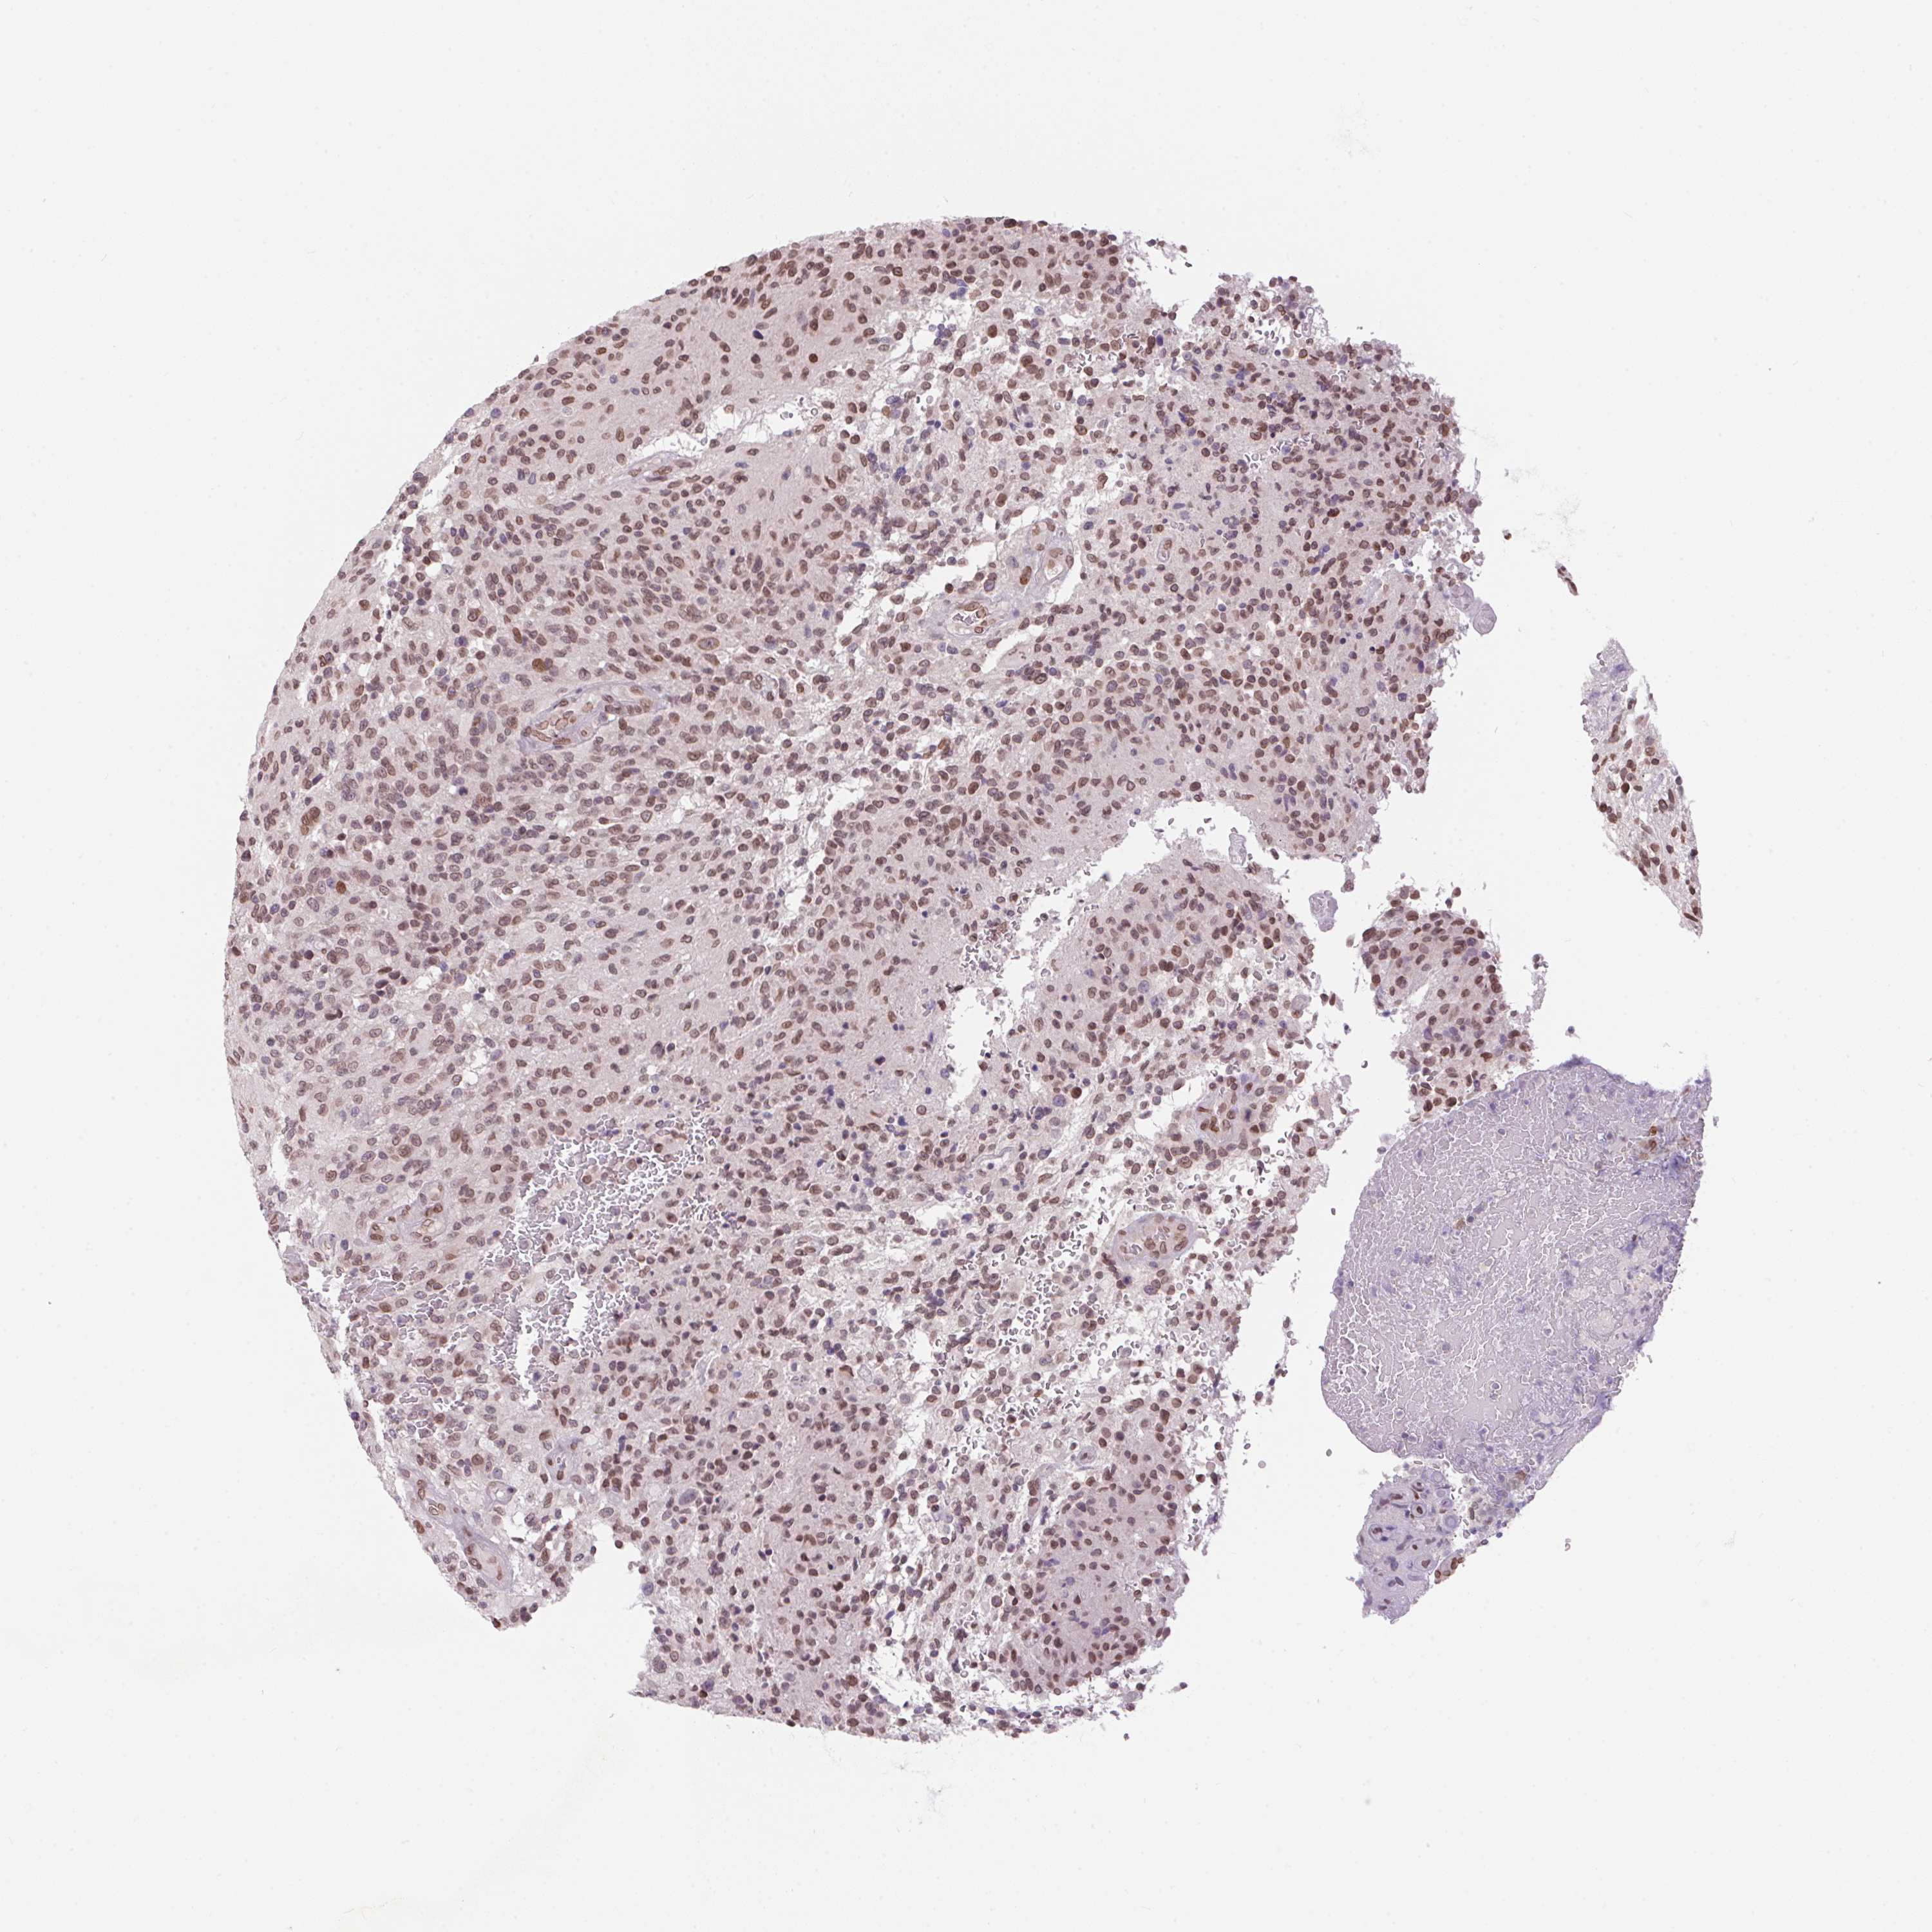

GLIOMA - Protein expressioni

A mouse-over function shows sample information and annotation data. Click on an image to view it in a full screen mode. Samples can be filtered based on level of antibody staining by selecting one or several of the following categories: high, medium, low and not detected. The assay and annotation is described here.

Note that samples used for immunohistochemistry by the Human Protein Atlas do not correspond to samples in the TCGA dataset.

Antibody stainingi

Antibody staining in the annotated cell types in the current human tissue is reported as not detected, low, medium, or high, based on conventional immunohistochemistry profiling in selected tissues. This score is based on the combination of the staining intensity and fraction of stained cells.

Each image is clickable and will lead to virtual microscopy that enables deeper exploration of all samples and also displays staining intensity scores, fraction scores and subcellular localization as well as patient and tissue information for each sample.

Antibody HPA057160

Staining

High

Medium

Low

Not detected

Intensity

Strong

Moderate

Weak

Negative

Quantity

>75%

75%-25%

<25%

None

Location

Nuclear

Cytoplasmic/membranous

Cytoplasmic/membranous,nuclear

Glioma, malignant, Low grade

Glioma, malignant, High grade